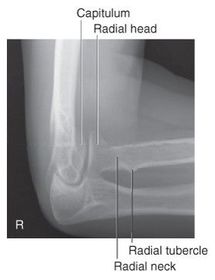

What is in profile for a lateral oblique elbow? radial head radial neck capitulum